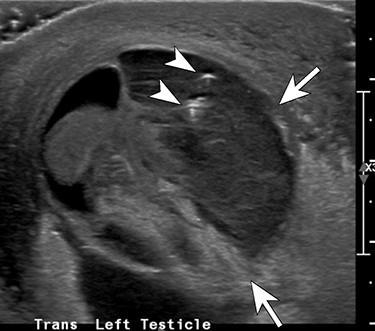

An 11-year-old male presents to the Emergency Department with chief complaints of fever, abdominal pain, nausea and non-bloody vomitus. The patient has no significant past medical history except for a weight that is >95th percentile. The pain started in the periumbilical area and became more generalized. Physical exam showed right lower quadrant (RLQ) pain with guarding with positive obturator sign but no rebound tenderness. An abdominal ultrasound was performed; however, the appendix could not be visualized. The patient then underwent an abdominal computed tomography (CT) that showed a perforated appendicitis. He was immediately taken to the operating room for laparoscopic appendectomy. A perforated appendix with free intraperitoneal pus identified in multiple abdominal quadrants during the operation. The appendix was successfully removed and the patient was transferred to post anesthesia care unit (PACU) in stable condition for recovery. Overnight, the patient developed increasing left scrotal swelling with mild tenderness. Doppler ultrasound showed normal arterial and venous blood flow in both testes, but demonstrated diffuse scrotal wall thickening and inflammation, more pronounced on the left. The patient’s condition failed to improve over the course of next few days and urology was consulted. Repeat ultrasound and a CT scan was obtained, which demonstrated a left intra-scrotal abscess (Figs 1 and 2). Surgical exploration was recommended. At the time of left scrotal exploration, a large intra-scrotal abscess extending into the inguinal canal was identified. Careful examination failed to identify a PPV. The abscess fluid was cultured, drained and the wound irrigated with antibiotic solution. A Penrose drain was placed. The cultures reported rare anaerobic growth of gram-negative rods. He was placed on meropenem and vancomycin at the recommendation of infectious disease. The drain was left in place and he was discharged home with amoxicillin–clavulanate. The drain was later removed on postoperative day five and he recovered fully without sequelae.

Transverse ultrasound image through the left hemiscrotum shows a complex fluid collection (arrows) including a few internal foci of gas (arrowheads) and debris.